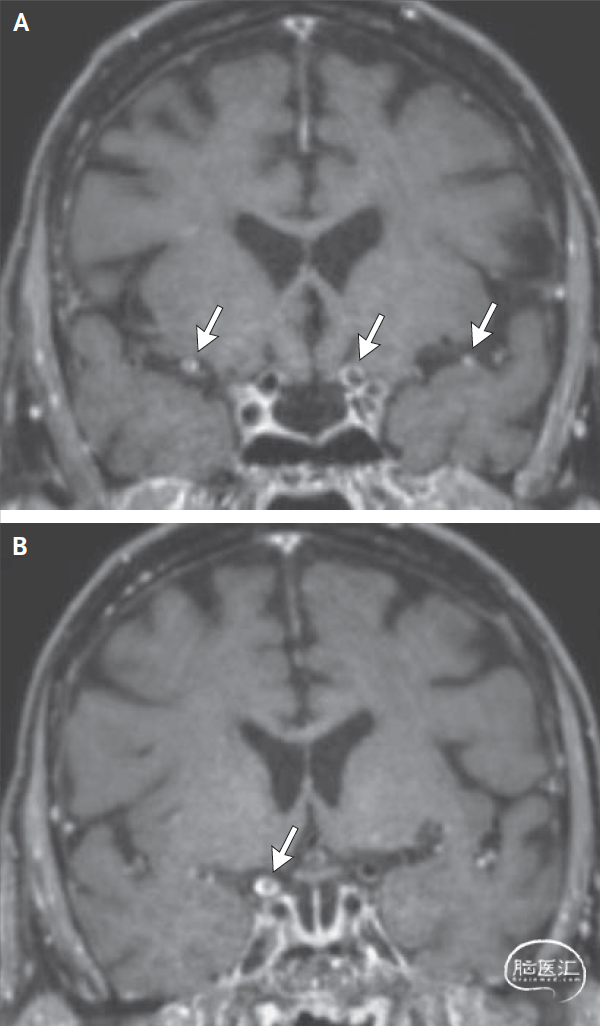

血管壁MRI:入院后,进行了高分辨增强血管病MRI(图2)。在该患者中,颅内血管壁MRI(图2)显示双侧颈内动脉和大脑中动脉的节段性同心强化,这可能表明非特异性炎症过程,如原因不明的血管炎。